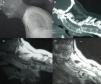

ResultadosSe identificaron un total de 6 lesiones cervicales en pacientes con espondilitis anquilosante: 2 presentaron fracturas por mecanismos de extensión y 4 por mecanismos de flexión. Todos los casos fueron intervenidos quirúrgicamente. Los 6 pacientes presentaron déficit neurológico postraumático y en 4 de ellos se observó mejoría neurológica tras la cirugía. Dos casos no mejoraron tras la cirugía. Uno de ellos presentó un grado de ASIA A y el otro paciente, que mejoró inicialmente con la cirugía, falleció por neumonía en el postoperatorio dos meses después.

ResultsA total of 6 cervical injuries were identified in a review of patients in whom ankylosing spondylitis had been diagnosed. Of these, 2 patients were associated with a hyperextension mechanism and 4 cases by flexion mechanism. Posttraumatic neurological deficits were demonstrated in all 6 cases and neurological improvement after surgery was observed in 4 of these cases. The two cases were not improved by the surgery was on a case by presenting a degree of Asia A and another patient who initially improved with surgery but died of pneumonia in the postoperative.